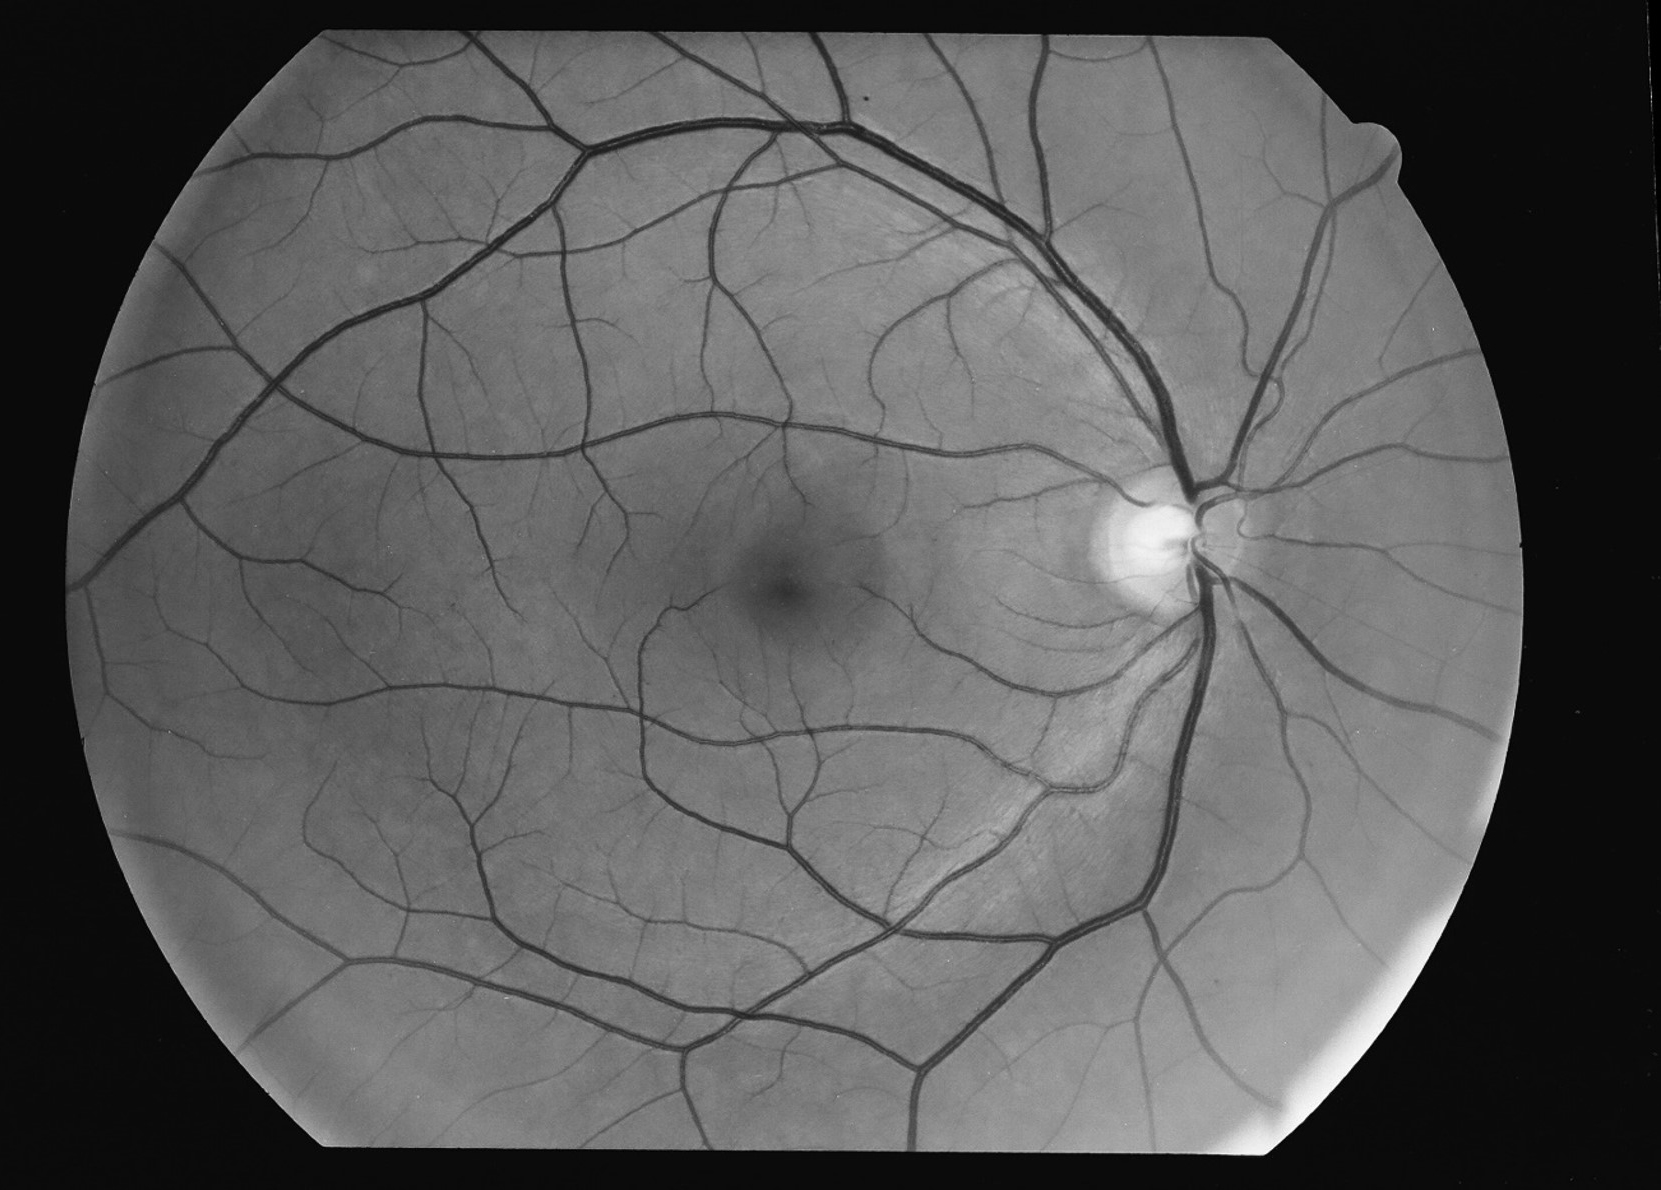

Kuva 24.

Tarkan näön alue: makula, fovea, foveola.